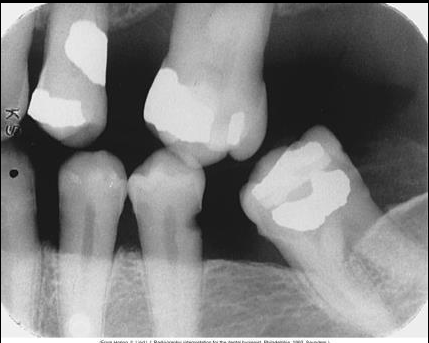

Describe Rampant caries.

Rampant caries refers to growing or spreading caries.

Advanced and severe affecting numerous teeth (can happen to both primary and permanent dentition)

Happens in children with poor dietary habits, nursing bottle syndrome or in adults with xerostomia (dry mouth) due to mediations.

Can also be a secondary condition to chemo radiation therapyÂ